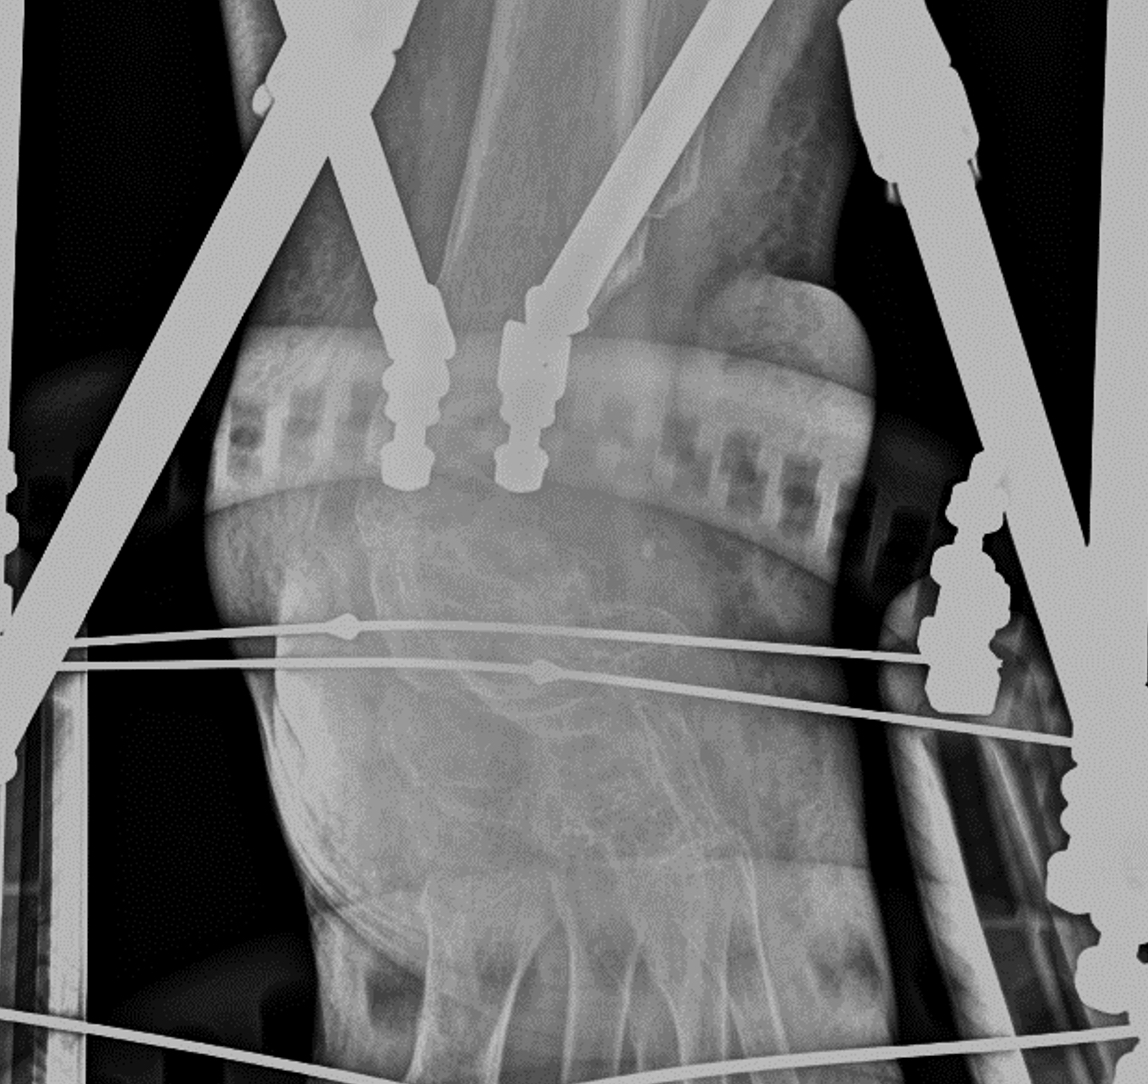

At this point, we used computer-generated hexapod external fixation technology. We applied a circular frame to realign the ankle joint by soft tissue distraction utilizing olive pins in the tibia, calcaneus, and metatarsals. It took 6 weeks to attain a corrected position (see first and second photos to left). Also, complete restoration of the joint space allowed restoration of the talar body. We also noted that the distraction process reduced the bulk of the lateral flap.